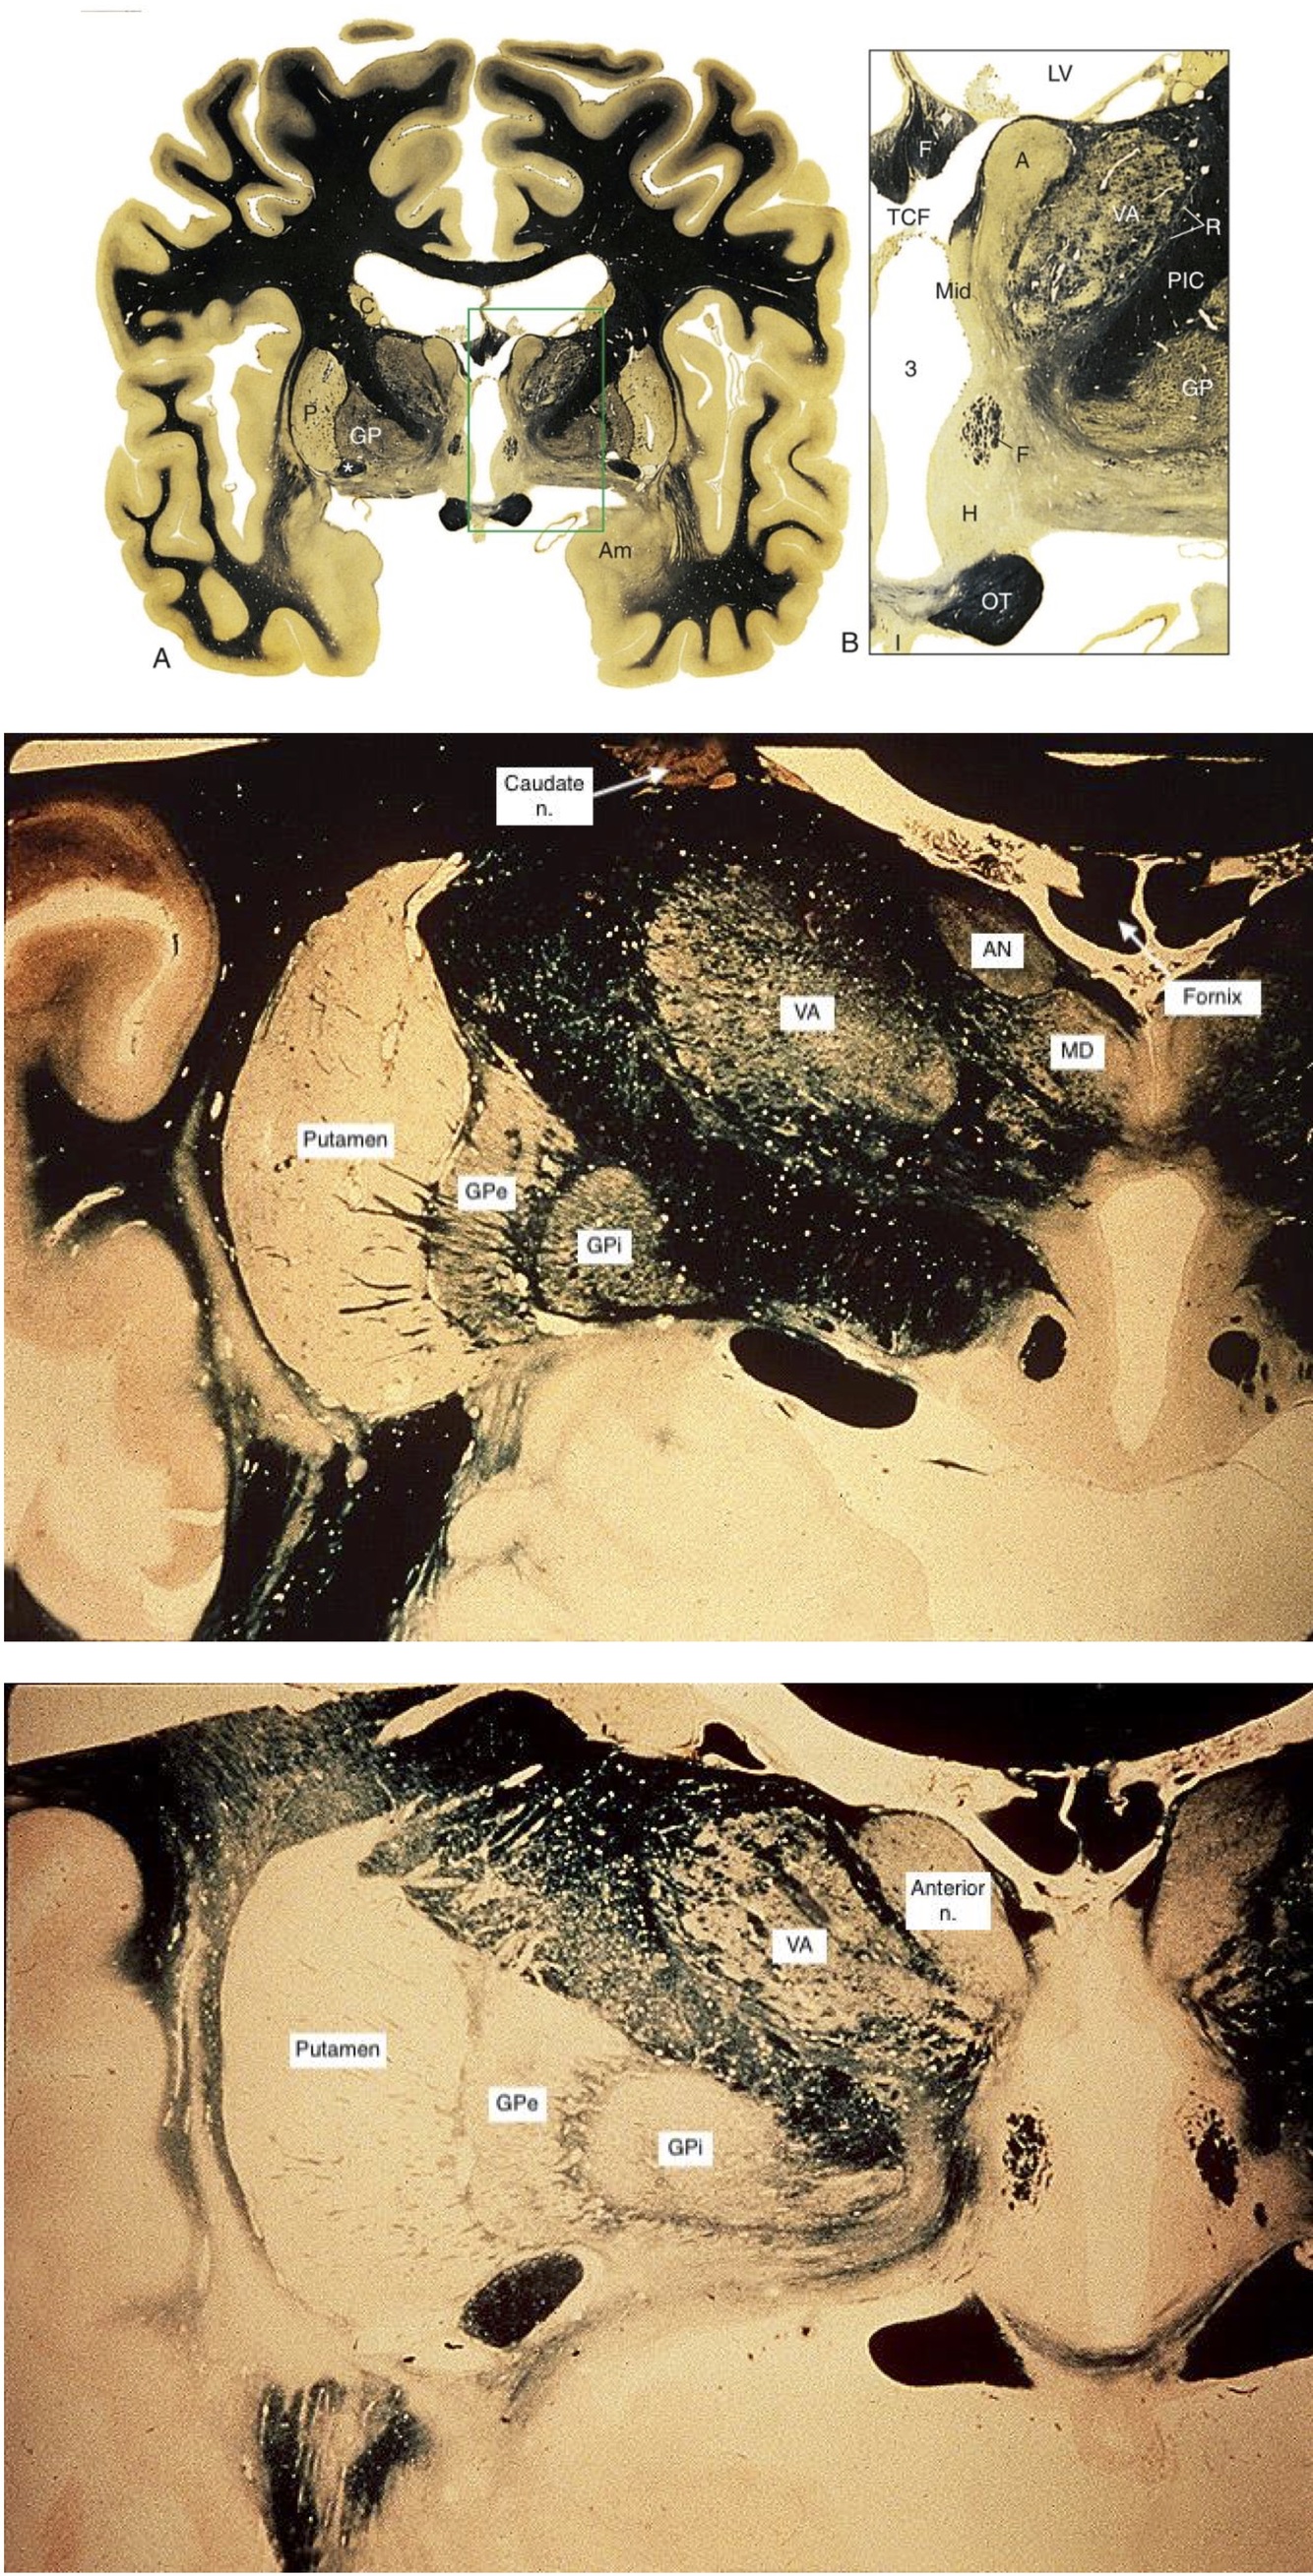

Rostral Thalamus